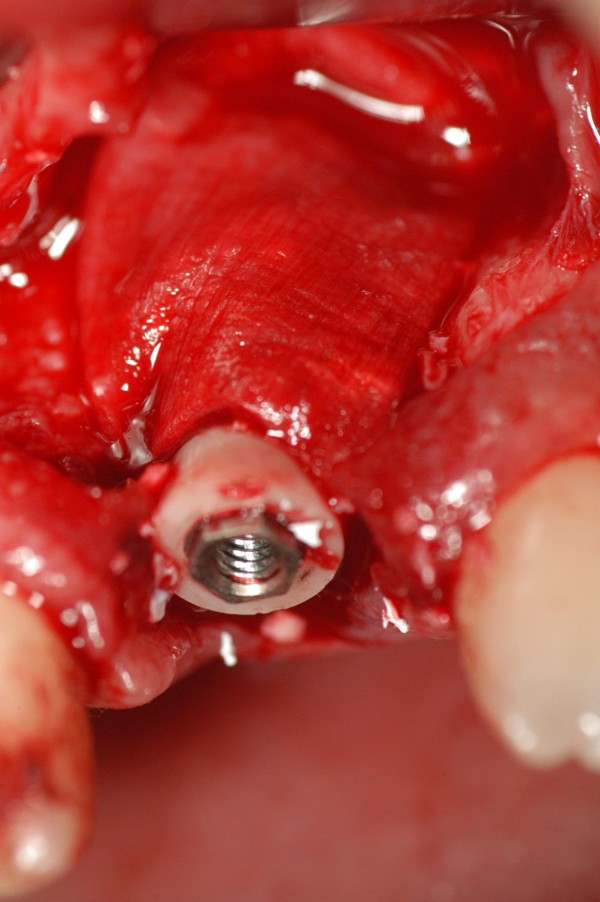

Abstract: Las fuerzas anterógradas traumáticas son en general las causantes de fracturas radiculares en el sector anterior de la boca. Desarrollo: El paciente se presenta a la consulta , con la fractura de una funda de porcelana inyectada en la zona cérvico palatina, solicitando simplemente la reparación en boca para evitar rozamientos linguales. Dicha funda con un perno colado en oro y su correspondiente endodoncia, habían sido realizadas en mi clínica varios años atrás, con un «aparente éxito total». Radiograficamente, se encuentra una fractura radicular cercana al tercio gingival Observada la oclusión de las piezas anteriores, podemos ver que el vínculo ideal de Acoplamiento, no se cumple, habiendo una relación de franco contacto la que ha provocado la fractura. Llevando al paciente a Oclusión en Relación Céntrica, podemos ver el espacio a nivel anterior, correspondiente a la centricidad mandibular. En esa misma posición , es dable percibir una faceta parafuncional mesial del primer premolar superior… …que antagoniza con una faceta parafuncional distal del canino inferior… ..constituyendo un plano inclinado que provoca la antelación mandibular o Discrepancia Horizontal, fracturando la raiz del incisivo central. Extraida la porción coronal de la raiz, pensamos en la realización de un Implante Inmediato, a pesar de la presencia de una fístula dado que se trataba de un central, decisión que obtuvo éxito implantario mas no estético, según veremos luego. Era fundamental conservar lo mas posible las tablas óseas, que de hecho había perdido la porción cervical Realizamos una incisión que conservara las papilas de las piezas adyacentes. Realizamos la exodoncia mediante un instrumento construido «ad hoc» que denomino: Con lo que obtenemos la preservación «ad integrum» de las corticales peridentarias remanentes. Instalamos entonces un implante T.B.R. de 15 mm de largo por 4 mm de diam. con cuello de zirconio de 3,5 mm …quedando tres espiras sin hueso por vestibular, producto de la tabla perdida, Incidimos el periostio a nivel apical del colgajo para obtener mayor paño quirúrgico, y legramos un bolsillo palatino sin incisiones de descarga, para la inserción de la membrana. Suplementamos la carencia ósea vestibular con «BIOSS» …e instalamos una membrana reabsorbible «BIOGUIDE» , que fijamos con el mismo implante, y calzamos por palatino. Suturamos Instalamos nuestra provisional previamente confeccionada, sobre un abuttment de titanio. Y controlamos radiograficamente Pasadas tres semanas del retiro de los puntos, observamos una cicatrización alta que nos muestra el anillo de zirconio del implante. ……………………………………………….. Transcurridos tres meses preparamos una nueva cirugía, dirigida a instalar un injerto autólogo de conectivo en el área del anillo, con un nuevo desplazamiento del colgajo vestibular. Tomamos tejido conectivo del paladar a nivel de los premolares, mediante una incisión mucosa «en libro», y disección del conectivo subyacente. Lo posicionamos en vestibular del anillo de zirconio y lo fijamos mediante sutura Y semanas después nos encontramos con un nuevo fracaso de orden estético. ……………………………………………….. En la actualidad, el caso esta estable , aún con su funda provisional, a la espera de un nuevo intento plástico, mediante Injerto Libre de Encia. ………………………………………………….. ESQUEMA MECÁNICO DEL FENÓMENO …que además de los hechos mostrados en el caso presentado, frecuentemente provocan en el sentido antero posterior los fenómenos de DISPERSIÓN ,en el maxilar superior…y de APIÑAMIENTO en el maxilar inferior. CONCLUSIONES: Además del rigor académico que nos convoca… esta; nuestra casa…nos otorga la confianza que solo da el saber que estamos siempre entre amigos, que cada vez son más. Por tanto es que debo decir: YO fui el responsable de dicha fractura… …porque… …..que hubiera sucedido si hubiera hecho todo el trabajo implantario sin ajustar previamente su oclusión? Seguramente a esta altura del caso…también hubiera fracasado el implante. Siempre decimos que se aprende de los errores más que de los aciertos, y Dr. Carlos A. Acuña Priano

Fig.22(Pie de foto: Membrana)

Fig.24(Pie de foto: funda provisoria en infraoclusión)

Fig.26(Pie de foto: Anillo de zirconio al descubierto)